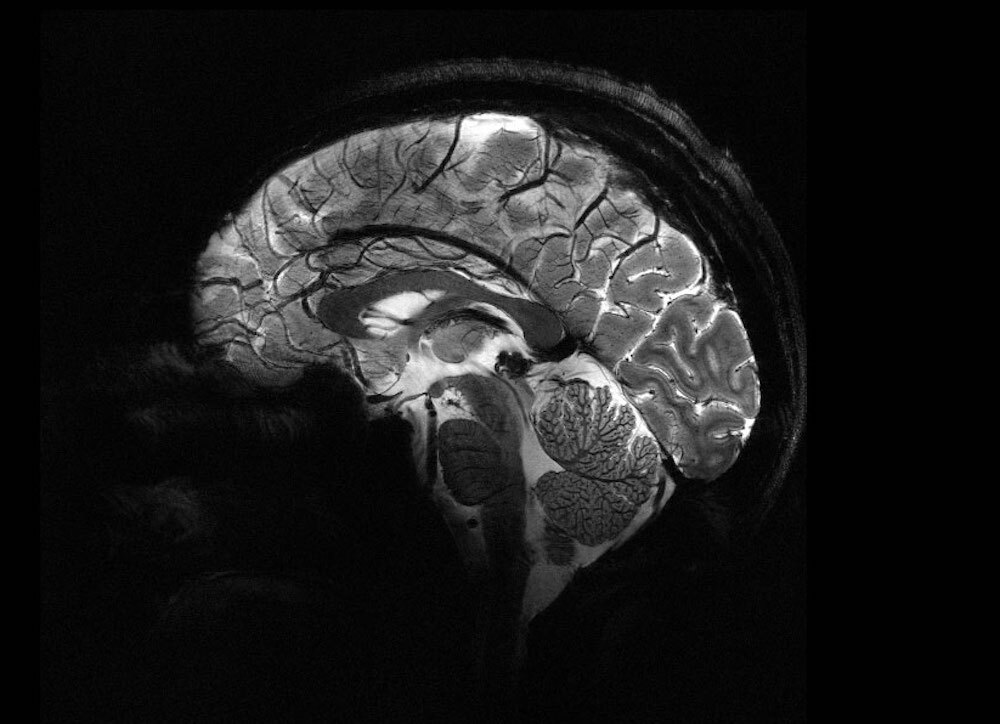

If a medical professional has ever had a hard time getting a needle into your veins, you’ll welcome this new gizmo from Adison Technology. By effectively turning your skin transparent, it makes needle sticks more accurate and therefore less painful.Con… Continue reading 3D vein viewer sees right through your skin